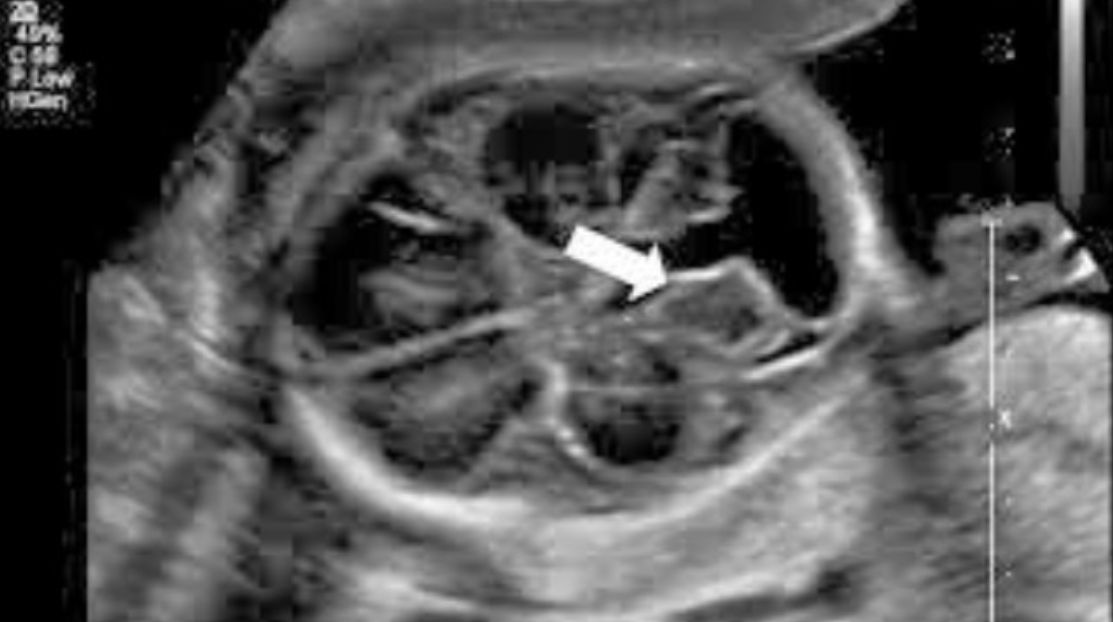

Giãn bể lớn hố sau ở thai nhi là một dị tật thai nguy hiểm, cần được phát hiện và điều trị sớm để tránh nguy cơ dẫn đến não úng thủy, ảnh hưởng lớn đến sức khỏe của thai nhi và của người mẹ.

Tổng quan Bệnh Giãn não thất cùng các dấu hiệu, triệu chứng, nguyên nhân, điều trị, cách phòng tránh và thông tin về các bệnh viện, phòng khám, bác sĩ chữa bệnh Giãn não thất.